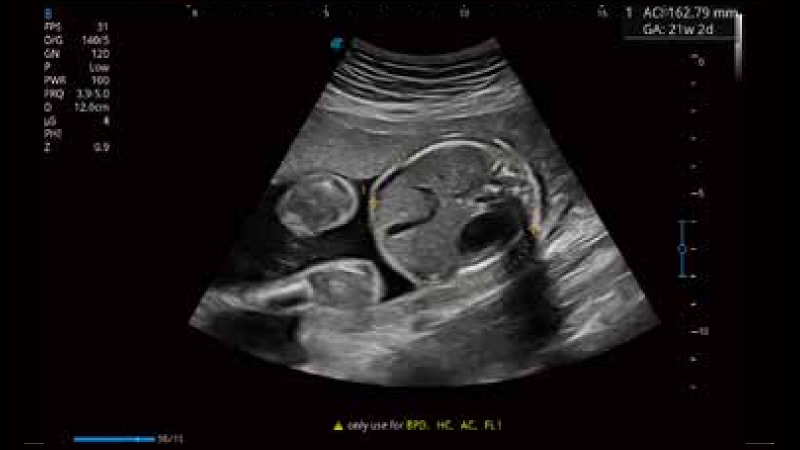

开立医疗通过不断的技术创新,为大众的生命健康提供持续关爱。P12 Plus采用全新一代超声成像平台,新平台旨在将真实还原组织解剖结构作为首要目标。平台采用全新集成化硬件模块,搭载新一代芯片,系统性能得到大幅提升,为您的诊断提供了丰富的临床信息。优异的图像表现,丰富的探头配置,全面的应用功能,为您日常诊断提供了可靠的助手。

凭借开立医疗先进的成像技术和优异的探头技术提供的清晰的图像表现,您可以更自信地做出临床决策。